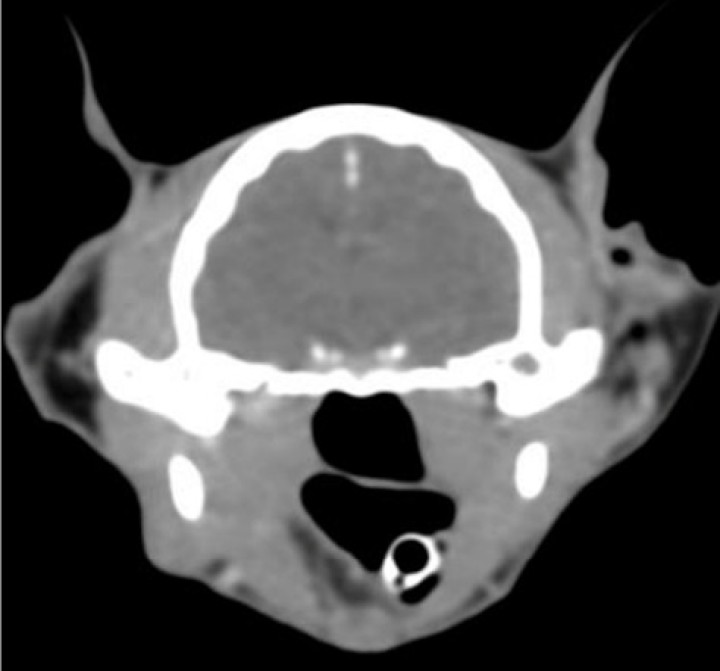

Finalmente, se realizó una tomografía computarizada (TC) de cabeza y tórax con el objetivo de identificar posibles metástasis regionales o a distancia, así como para facilitar una adecuada planificación quirúrgica. La TC no evidenció lesiones osteolíticas, linfadenopatías ni signos de diseminación metastásica, incluido el sistema nervioso central. Sin embargo, no fue posible descartar con certeza la invasión del nervio óptico, ya que la masa ocupaba por completo la cuenca orbitaria derecha, incluyendo el espacio retrobulbar y desplazando los vasos sanguíneos en dirección dorsocraneal. Esta extensión dificultó la evaluación precisa de la infiltración del nervio óptico y estructuras vasculares adyacentes. A pesar de ello, los hallazgos confirmaron la localización primaria de la masa en la región ocular derecha y la ausencia de diseminación a otros órganos en el momento del estudio (Figs. 3 y 4).

Figura 4

Imagen tomográfica transversa donde, a nivel intracraneal, no se evidencia ninguna lesión intra o extraaxial, no existe desplazamiento de la línea media, ni edema cerebral. La captación de contraste es normal y simétrica. Sin alteraciones meníngeas. Imagen cedida por el Hospital Bluecare.